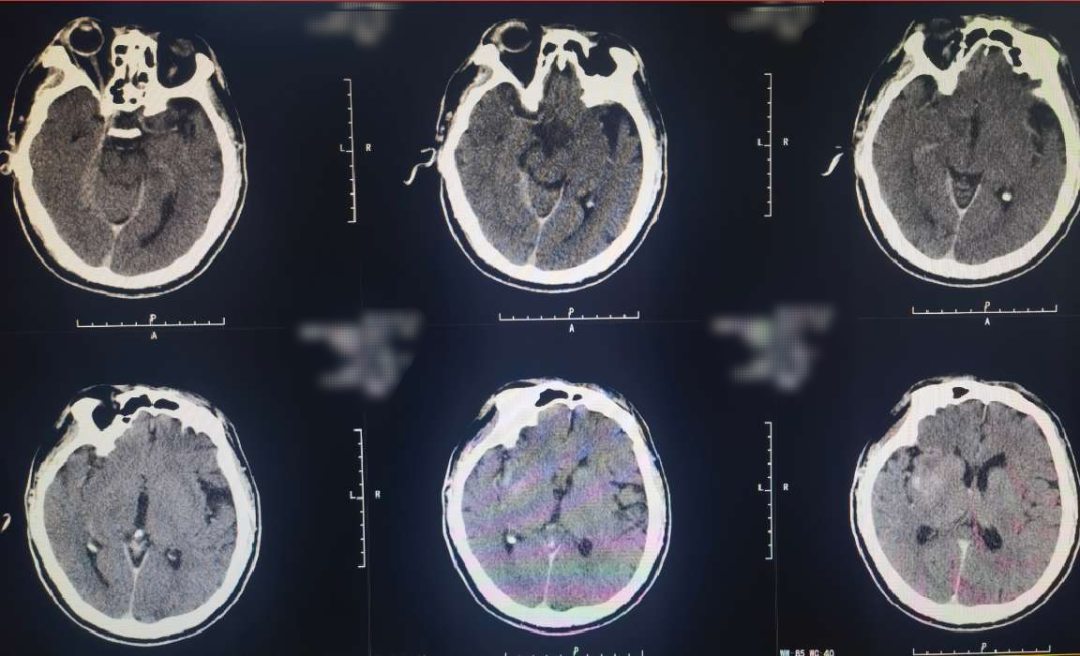

Cranial CT revealed a hyperdense sign in the right middle cerebral artery.

Immediate postoperative CT showed no secondary hemorrhage but mild contrast retention.

10-day postoperative follow-up cranial CT showed infarction in the right cerebral hemisphere.